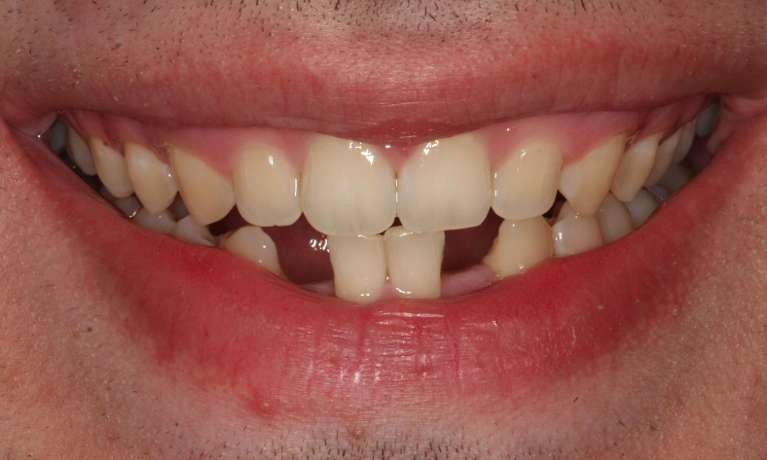

This young dad had four congenitally missing upper teeth. He had a quick orthodontic treatment and a large span bridge placed in as a teenager. He never smiles with teeth showing.

After many years of wear and tear, some of the work started to break and fail. We removed the defective bridges, managed to save all the existing teeth and placed four implant supported crowns in. The patient is very happy to be able to smile confidently now.